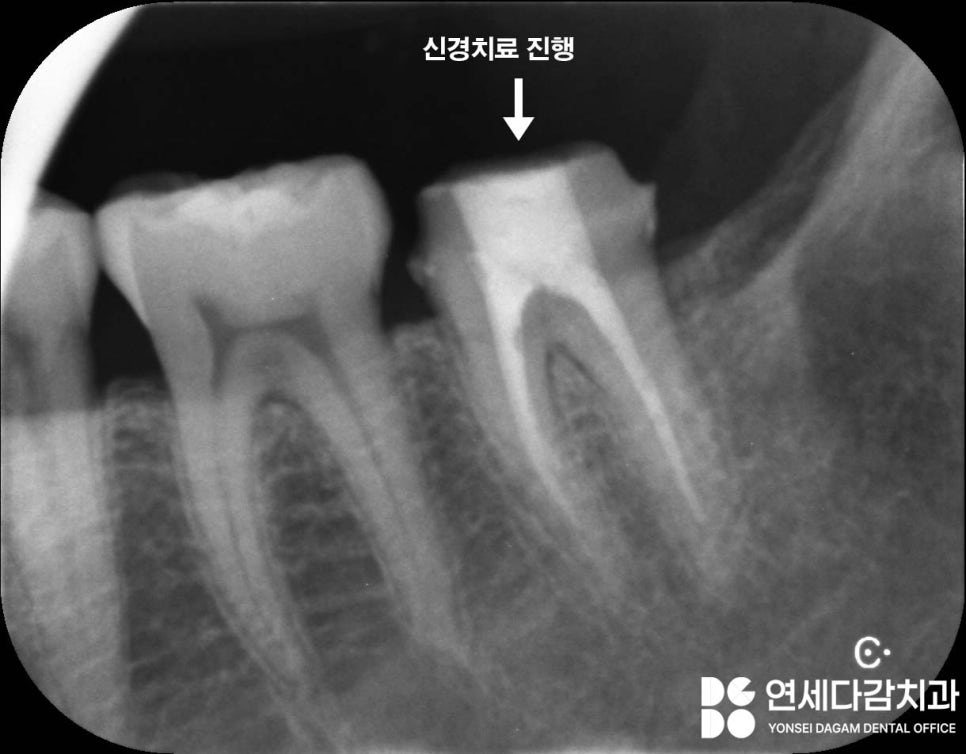

크라운을 씌운 뒤에도 통증이 지속되는

상황에는 추가적으로 근관치료를 통한

적극적인 치료가 필요합니다.

왜 통증이 지속될까?

치아 균열이 심한 경우에는

크라운을 씌워도 통증이 있을 수 있습니다.

가락시장역 치과 에서 표시한 것처럼

균열이 치아 내부의 신경까지

도달한 경우에는

감염이나 염증이 쉽게 발생할 수 있어

이런 경우에는 근관치료를 통해

감염원과 통증을 없애줘야 됩니다.